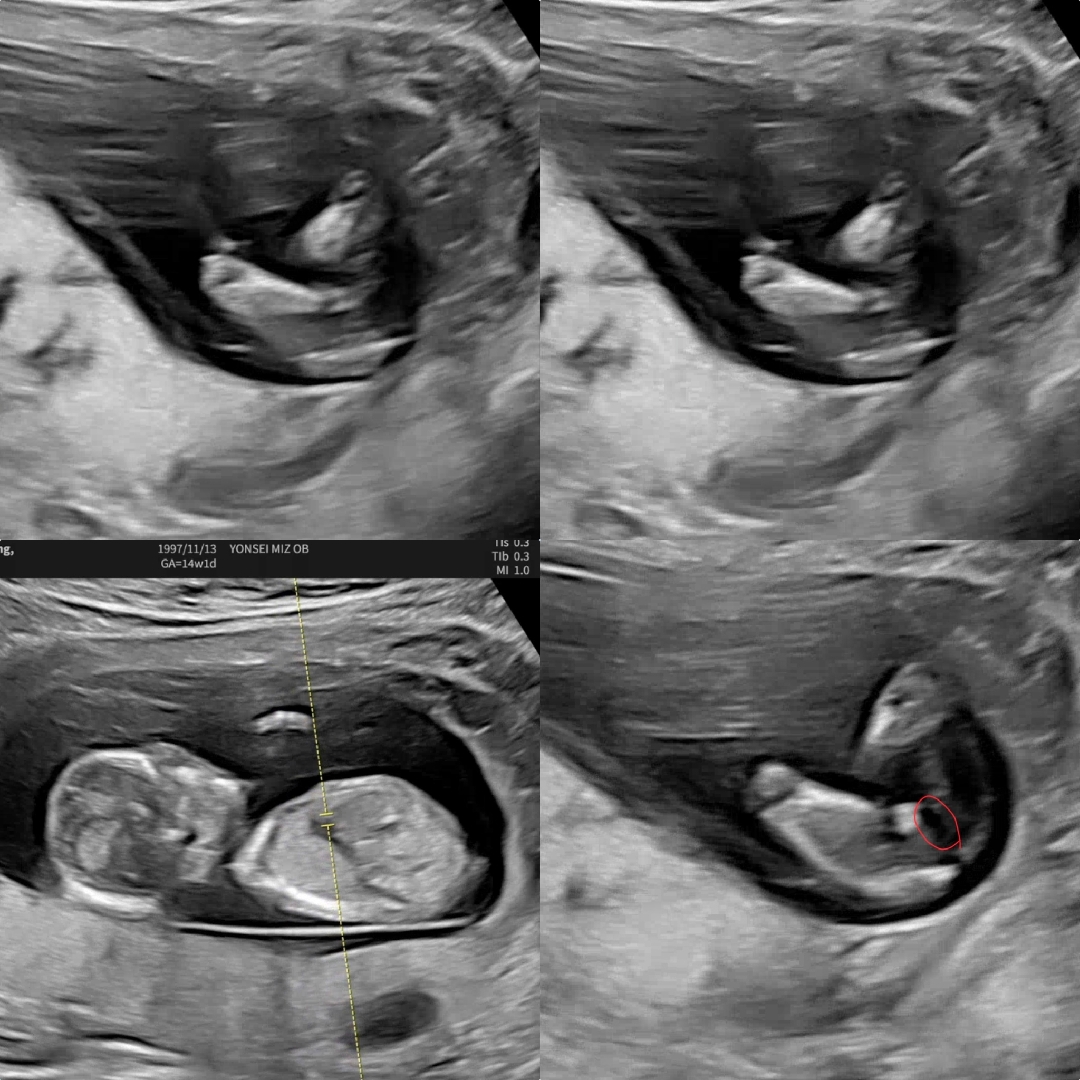

14주1일차, 7살 차이 둘째 초음파 좀 봐주세요!!

성기가 보이다 안 보이다해서 여아도 양수 때문에 부으면 남아처럼 보일 수 있다고 다음번 촘파를 봐야 될 것 같다고 하시더라구요 ㅠㅠㅠㅠ 그래서 15주 4일차인 어제 비염약 타러 가면서 촘파 보려고 했는데 원래 다음 예약일인 20일에 오라고 안 보여주시더라구요😢 그리고 남아 성기라면 동그라미친 저 부위가 다리 사이 정중앙이라 저기에 하얗게 돌출되어 있어야 한다는데 살짝 왼쪽 대각선에 위치해있어서.. 애매하다는데 어때 보이시나요?